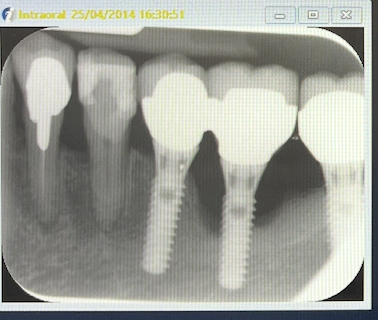

radio initiale 25/04/2014

Examen clinique: gencives oedémateuses, saignements au sondage, poches 4-5 mm, gencive attachée autour de l'implant 36, pas surcharge occlusale.

Examen radiologique: alvéolyse horizontale et perte osseuse au niveau de l'implant 36.